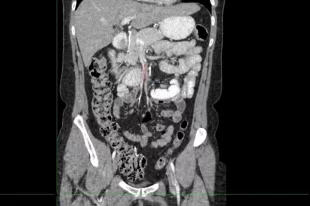

Красноярку с редким заболеванием Уилки прооперировали хирурги 20-й больницы

Красноярку с редким заболеванием Уилки прооперировали хирурги 20-й больницы 08.04.2026 11:42

Из-за осложнений женщина потеряла в весе.